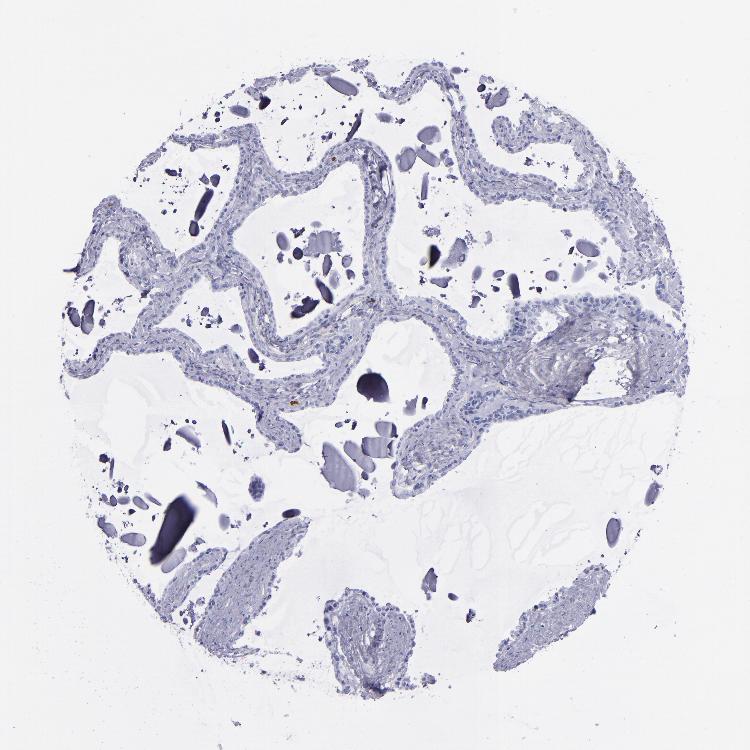

TISSUE PRIMARY DATA SEMINAL VESICLE Show tissue menu

SEMINAL VESICLE - Antibody stainingi

Antibody staining in the annotated cell types in the current human tissue is reported as not detected, low, medium, or high, based on conventional immunohistochemistry profiling in selected tissues. This score is based on the combination of the staining intensity and fraction of stained cells.

Each image is clickable and will lead to virtual microscopy that enables deeper exploration of all samples and also displays staining intensity scores, fraction scores and subcellular localization as well as patient and tissue information for each sample.

Antibody HPA042455Antibody HPA043579Antibody HPA049348Antibody CAB002491Antibody CAB016271

Glandular cells Not detectedMediumNot detectedNot detectedNot detected